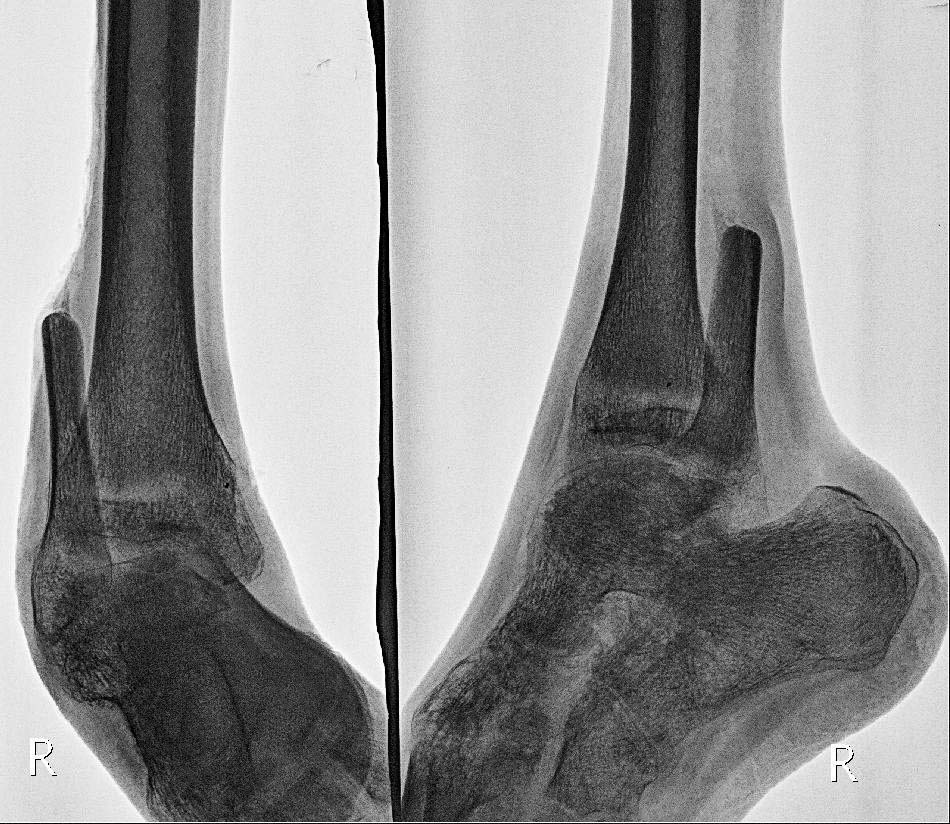

На лечении находится пациент 19 лет, получивший травму в августе 2014года, по поводу чего проходил лечение в ряде ЛУ. В настоящее время имеем правую стопу,вэквино-варусном положении, дефект диафиза малоберцовой кости около 8 см. с дефектом мышцнаружной группы мышц правой голени, кожный покров восстановлен пластически.

Прирентгенографии: подвывих стопы кнутри, выраженный остеопороз. Левая нижняя конечностьэкзартикулирована в тазобедренном суставе. Планируем первым этапом устранить деформациюв аппарате Илизарова, затем выполнить артродез. Здесь возник вопрос: выполнить артродезтолько голеностопного или совместно с подтаранным суставом. Каково Ваше мнение?

Добрый день. Для обсуждения метода лечения желательно на форум представить рентгенографию голени,голеностопного сустава,стопы и фото голени пациента.Если нет дегенеративных изменений в подтаранном суставе, то лучше ограничится артродезом голеностопного сустава.

Добавляю фото и рентгенограммы.

Учитывая выраженные изменения в подтаранном суставе и для восстановления опороспособности конечности целесообразно выполнить панартродез в аппарате.

Уважаемые коллеги! Спасибо за советы! Сегодня выполнен артродез голеностопного сустава винтами, подтаранный сустав решили оставить "на потом".